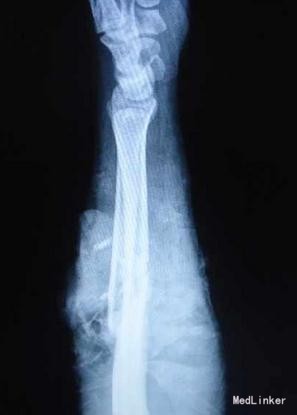

患者36岁,因“电锯锯致左前臂疼痛出血伴畸形1小时”入院

左前臂中段背侧见U形皮瓣,长约16厘米,蒂长约8厘米,蒂宽约5厘米,翻向远侧;创面轻度污染,伸肌群断裂,尺桡骨骨折端外露,有搏动性出血。1-5指背伸障碍,4、5指感觉减退,桡动脉搏动存,尺动脉搏动未触及。 X线:左尺桡骨中段粉碎性骨折,断端成角错位。

左前臂切割伤:左尺桡骨开放粉碎性骨折,伸肌群断裂,尺侧血管神经束断裂。 手术行清创+尺桡骨骨折内固定+肌腱缝合+尺神经吻合术,术中见尺桡骨断端不整,予修复后钢板内固定,并取人工骨条植骨;术中见指端血供可,指腹饱满,予结扎骨间动脉及尺动、静脉,吻合尺神经。并予伸肌群一一对应缝合。见皮肤张力高,无法完全对合,遗留尺背侧约5.0*4.0厘米创面。术后见指端血供可,毛细血管充盈时间1-2秒。术后第3天患肢肿胀明显,拆除部分缝合线,挤压后有淡黄色脓液流出,伴恶臭,且有伸肌群的坏死;指端血供可。普通培养基做细菌培养及药敏示:溶血性葡萄球菌。每日予甲硝唑+阿米卡星以及双氧水冲洗创面。